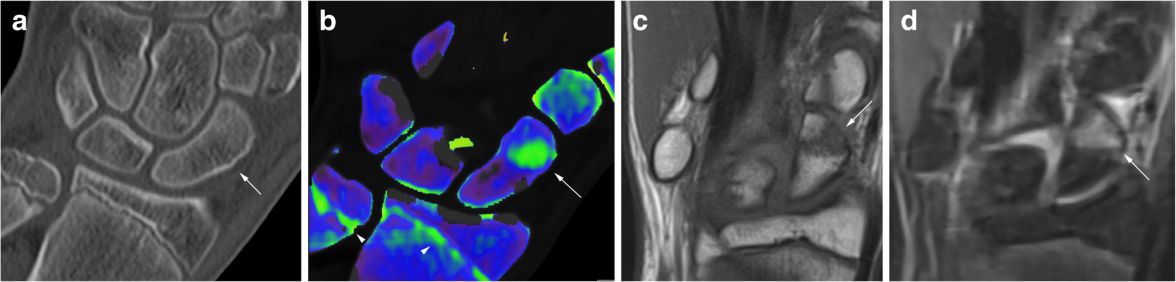

双能量骨髓水肿:舟状骨